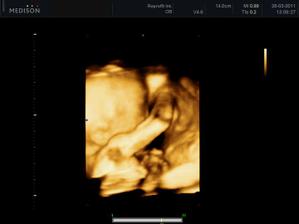

25.3.2011 - 3D utz - tak konečně víme, kdo nám to bydlí v bříšku - je to neuvěřitelný, ale je to malá princezna, hurááá hurááá je to holka - jsme moc šťastní - je to celej táta - i slza ukápla a tátovi taky.A kočenka s panem doktorem opět nespolupracovala, takže maminka opět chodila po chodbě jak trdlo, nakonec se umoudřila a přelehla si na druhej bok, nakonec se nám postavila na hlavu, asi jako už mě nechte být, no byla to sranda - krásný zážitek a nakupujeme růžovou 🙂 - měříme 24 cm a vážíme 320 g